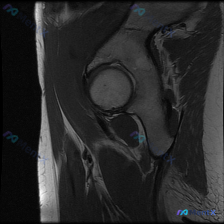

单张髋部MRI T1序列冠状位,盂唇问题看这里

整理到一个髋关节MRI分析的内容,仅提供了单张T1序列冠状位图像,临床关注点是盂唇病变。先看一下这张图像的客观描述:

骨骼结构:股骨头圆形,轮廓光整,骨皮质连续,骨髓信号均匀;髋臼形态连续,骨皮质清晰;大转子区域骨皮质完整。

关节间隙:宽度基本对称,无明显狭窄,无异常信号填充。

软骨与盂唇:股骨头表面软骨厚度均匀,信号中等;盂唇呈低信号,形态连续,边缘无异常增厚或分离。

软组织:周围肌肉形态体积正常,关节囊无积液,神经血管束走行区域无占位。

现在问题来了:仅根据这张T1序列冠状位图像,大家对盂唇情况怎么看?